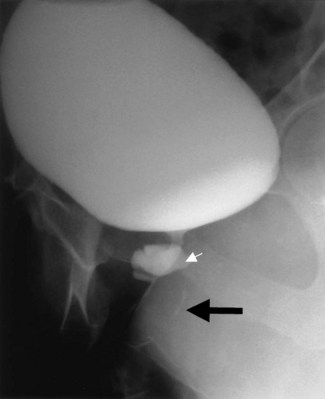

Vesicovaginal fistulae (VVF) are the most common acquired fistula of the urinary tract (Gerber and Schoenberg, 1993) and have been known since ancient times (Fig. 77–1). However, it was not until 1663 that Hendrik von Roonhuyse first described surgical repair of VVF by denuding the fistula margins and then reapproximating them with sharpened stiff swan quills (Margolis and Mercer, 1994). Johann Fatio is generally credited with the first successful VVF repair, in 1675, using von Roonhuyse’s technique (Falk and Tancer, 1954). In 1838, using leaden suture, John Peter Mettauer was the first U.S. surgeon to claim a successful VVF closure (Kight, 1967). In 1852, James Marion Sims published his now famous surgical series describing his method of surgical treatment of VVF using silver wire in a transvaginal approach (Sims, 1852). Of note, it was not until his 30th attempt at closure of VVF that he achieved success. However, Sims remains the subject of considerable debate regarding his ethics (Richardson, 1994; Sartin, 2004), because it is unknown whether the patients in his surgical series were willing and consenting participants (all were African-American slaves in pre–Civil War America). He was later to become one of the great figures in the history of operative gynecology. The first successful transabdominal approach to VVF repair was reported by Trendelenburg in 1888, and the concept of an interpositional flap was first proposed and reported in 1928 by Martius, who used a labial fat pad.

Figure 77–1 Voiding cystourethrogram demonstrates filling of the vagina with voiding due to a post-hysterectomy vesicovaginal fistula.